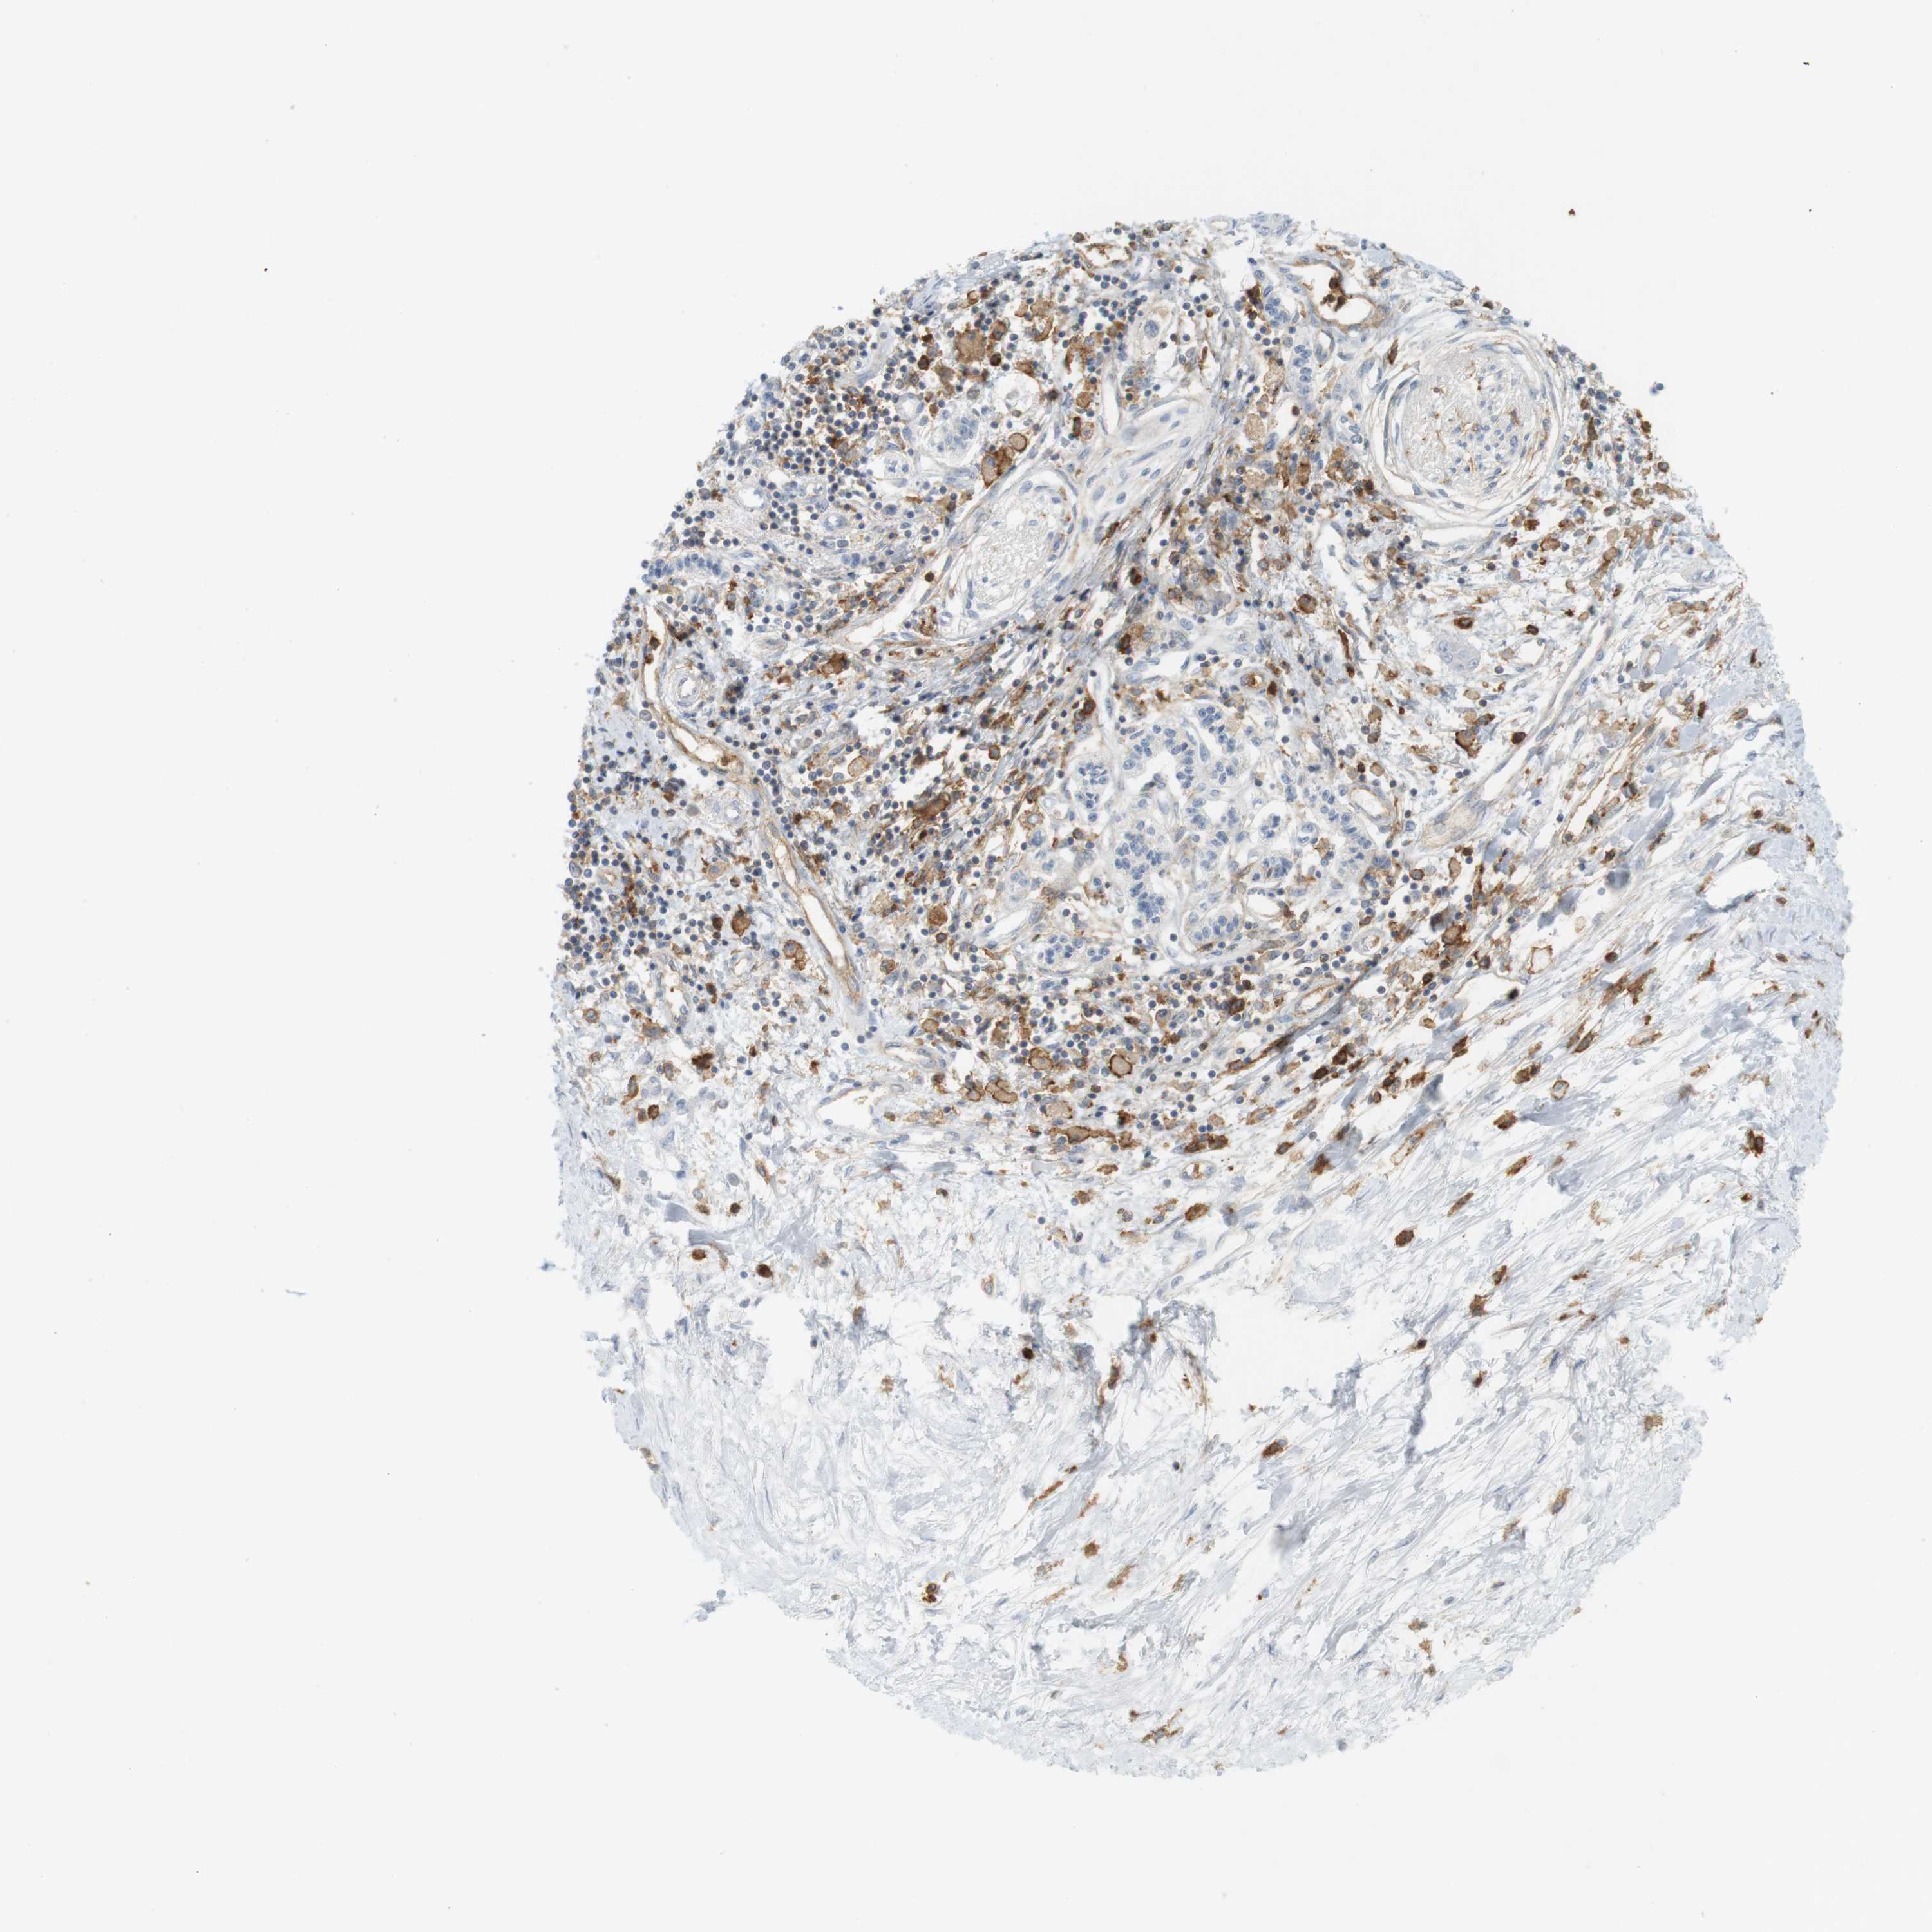

PANCREATIC CANCER - Protein expressioni

A mouse-over function shows sample information and annotation data. Click on an image to view it in a full screen mode. Samples can be filtered based on level of antibody staining by selecting one or several of the following categories: high, medium, low and not detected. The assay and annotation is described here.

Note that samples used for immunohistochemistry by the Human Protein Atlas do not correspond to samples in the TCGA dataset.

Antibody stainingi

Antibody staining in the annotated cell types in the current human tissue is reported as not detected, low, medium, or high, based on conventional immunohistochemistry profiling in selected tissues. This score is based on the combination of the staining intensity and fraction of stained cells.

Each image is clickable and will lead to virtual microscopy that enables deeper exploration of all samples and also displays staining intensity scores, fraction scores and subcellular localization as well as patient and tissue information for each sample.

Antibody HPA054437

Antibody HPA058511

Antibody CAB002776

Antibody CAB015122

Adenocarcinoma, NOS

Adenocarcinoma, metastatic, NOS